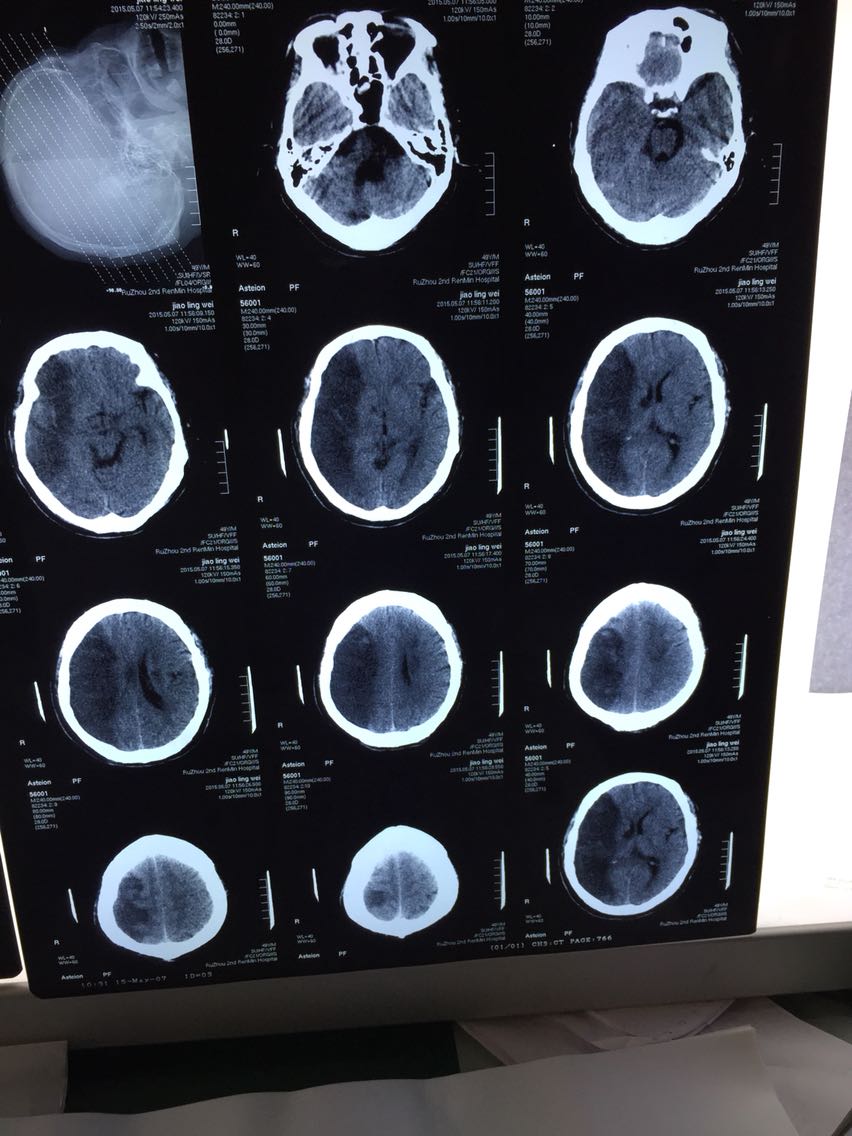

患者有10余年高血压,糖尿病,6年脑梗塞病史,现左侧肌张力高,肌力2级,意识模糊,